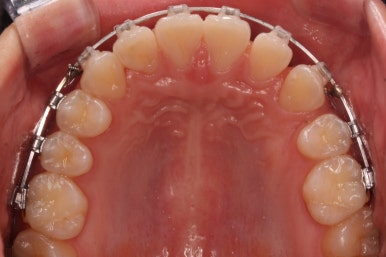

부산교정 키다리아저씨치과에서는 이번에 마이크로 임플란트라는 장치를 추가로 사용하였습니다.

잇몸뼈에 교정 치료기간동안 잠깐 사용하는 매우 작은 스크류인데요. 단단히 고정시켜 놓고, 어금니를 당겨오는데 사용합니다.

틈을 줄여주고, 어금니를 당겨오고 중앙선을 맞춰줍니다.

점점 단계가 진행될수록 얼굴의 중앙~윗니의 중앙~아랫니의 중앙이 점점 맞아가고 있음을 알 수 있습니다.

위아래 중앙도 어느 정도 맞아가고 있고, 발치를 한 자리와 결손치아 부위의 틈도 거의 없어져 가고 있습니다.

부산교정 키다리아저씨치과에서는 이번 환자분은 아래 앞니를 3개로 마무리하는 것이 아니라 송곳니를 끌어 당겨와서 앞니처럼 마치 앞니가 4개 있는 것처럼 마무리를 할 계획이어씨 때문에 정면에서 바라보았을 때 앞니 하나가 없는 느낌이 없이 어느 정도 중앙을 맞출 계회이였고, 원할히 진행되고 있음을 알 수 있습니다.